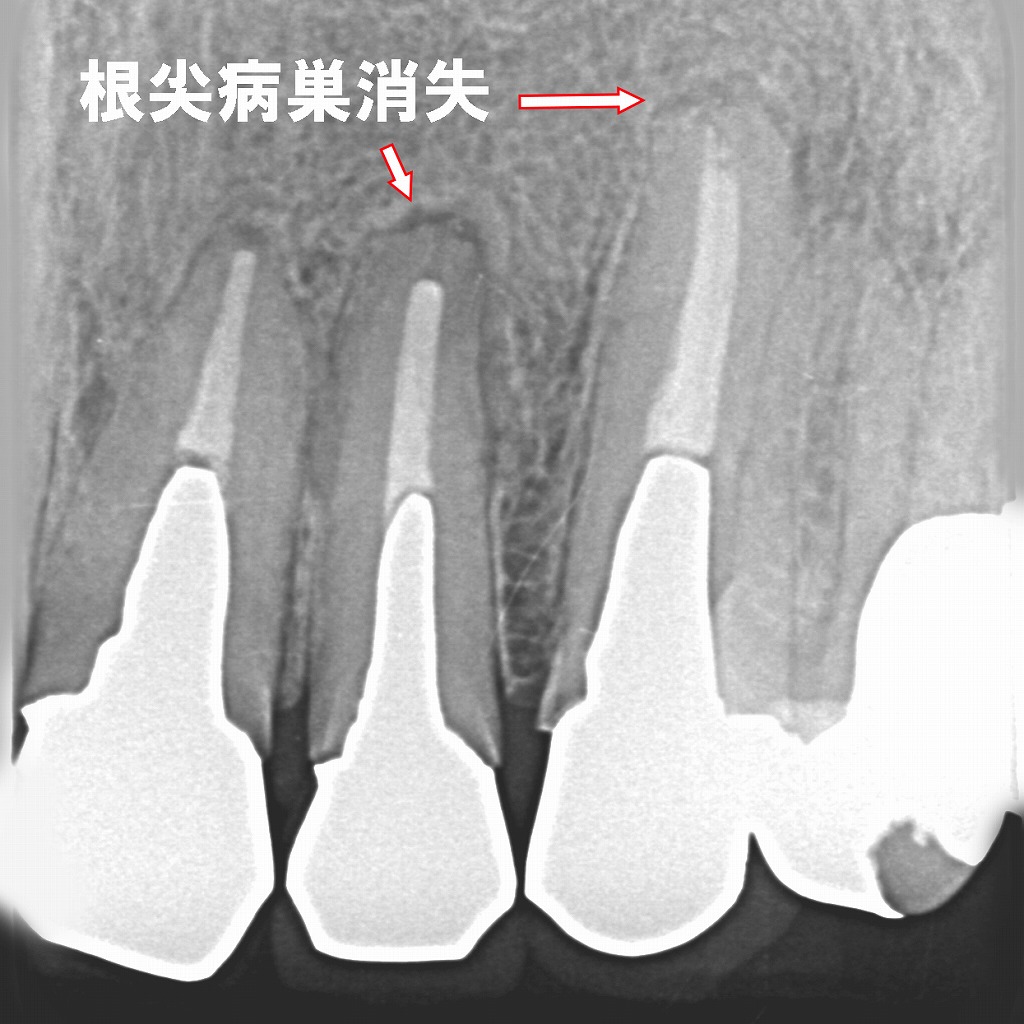

再根管治療後に根尖病巣が治癒

このX線画像は、前回の根尖病巣が治癒した再根管治療後の経過症例を示しています。以下のように説明できます。

🦷 所見の概要

- 対象歯:上顎右側2番(側切歯)・3番(犬歯)

- 画像の特徴:以前認められた根尖部のX線透過像(黒い影)が消失しており、周囲骨の構造が再生していることが確認できます。

- 診断名:根尖性歯周炎の治癒(根尖病巣消失)

🔍 治療の流れ

- メタルコアの除去

- 初回治療時に挿入されていた金属製ポストを慎重に除去。

- これにより、根管内部へのアクセスが確保されました。

- 再根管治療(リトリートメント)

- 旧充填材(ガッタパーチャ)を除去し、感染源となっていた細菌や壊死組織を徹底的に清掃・消毒。

- 根尖まで確実に根管充填を行い、密閉性を改善。

- 根尖病巣の治癒

- 数か月〜1年の経過で、骨の再生が進み、黒い透過像(病巣部)が消失。

- X線上で正常な骨の密度に戻っています。

- 最終補綴(メタルボンドクラウン)

- 治癒後、強度と審美性を両立するメタルボンド冠を装着。

- 噛み合わせ・見た目ともに良好な状態が維持されています。

🩺 まとめ

この症例は、根管治療のやり直しによって感染を除去し、歯を抜かずに治癒へ導いた成功例です。

根尖部の病巣は完全に吸収され、周囲骨が再生していることから、再根管治療の効果が明確に確認できます。